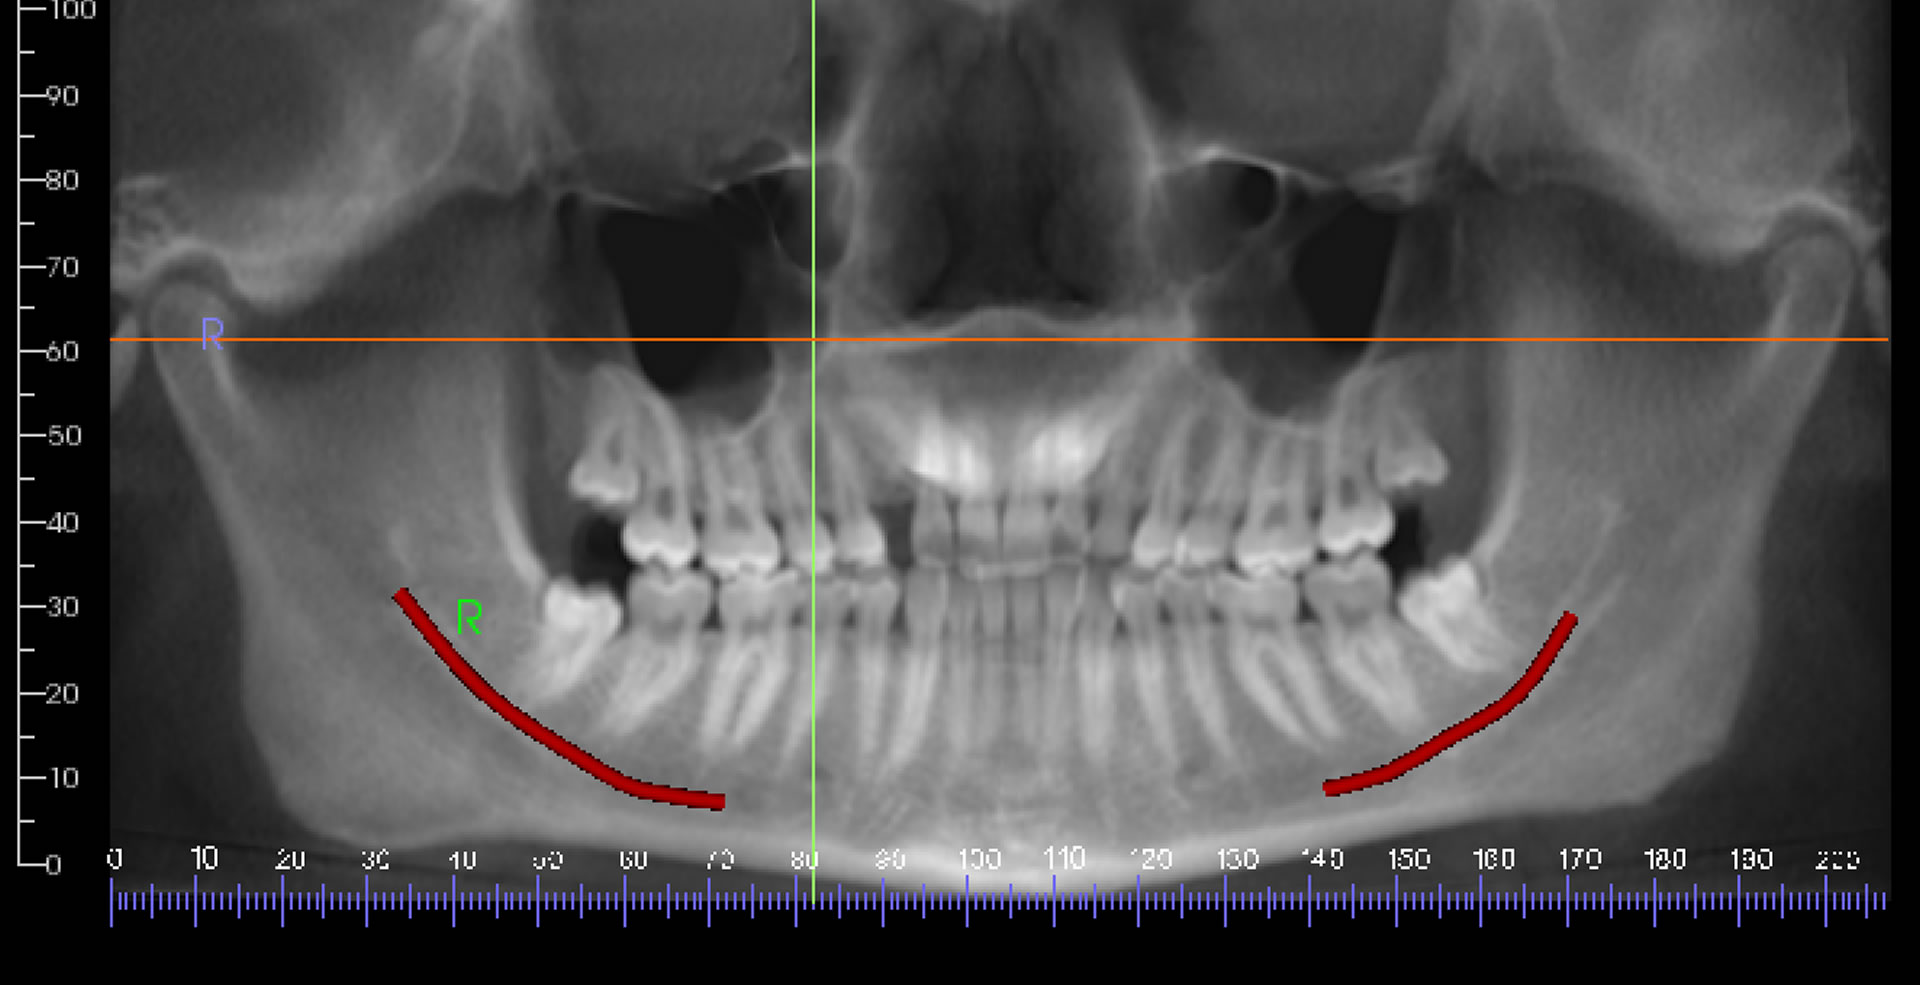

Panoramic Radiographs Dental Definition at Richard Maston blog Radiology Dental Definition We need to understand how they work and interact with the body to be able to make a sound clinical. Dental radiology includes the periapical film (pax) to visualize periapical pathology, bitewing films to identify occlusal and interpromimal dental caries,. Radiographs are an important diagnostic tool that supplement our clinical findings. Radiology Dental Definition.

10. Panoramic Imaging Pocket Dentistry Radiology Dental Definition Radiographs are an important diagnostic tool that supplement our clinical findings. Dental radiology includes the periapical film (pax) to visualize periapical pathology, bitewing films to identify occlusal and interpromimal dental caries,. We need to understand how they work and interact with the body to be able to make a sound clinical. Radiology Dental Definition.